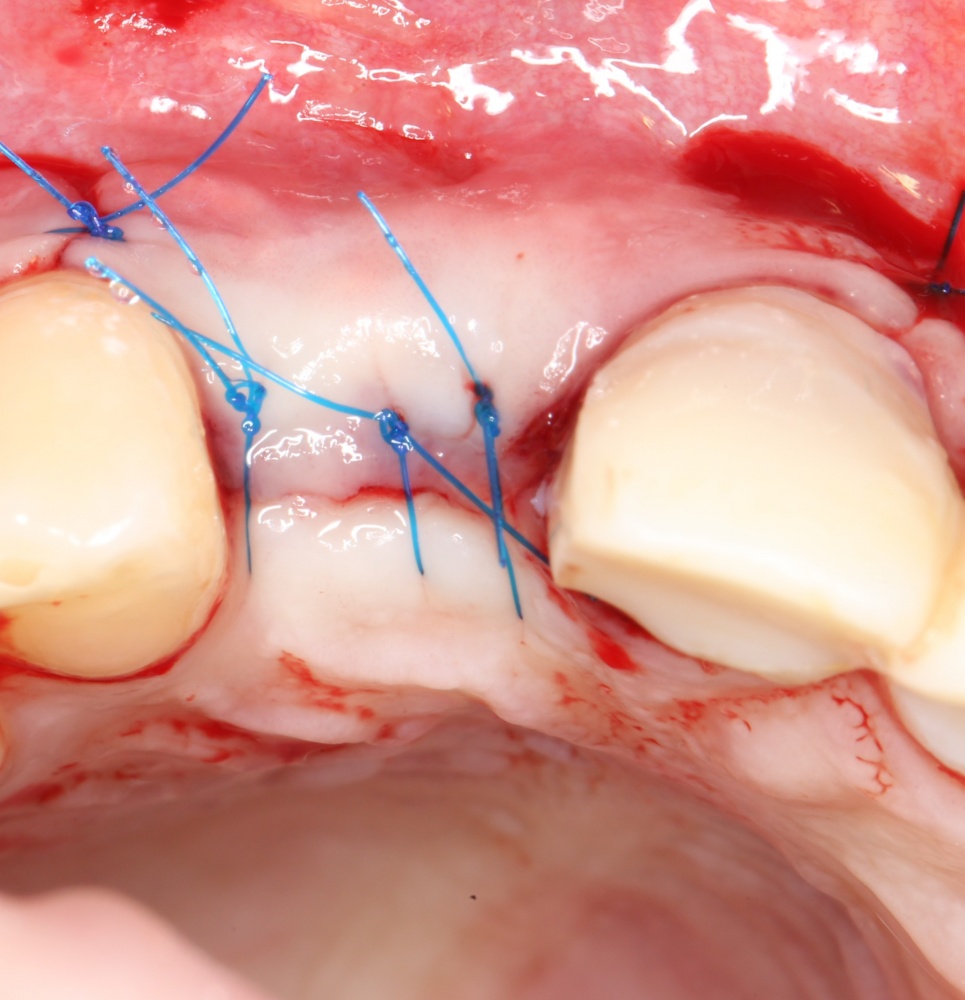

Если на этапе разреза и формирования раны всё сделано правильно, то наложение швов не вызывает особых трудностей. Периостотомия или послабляющие разрезы на периосте не требуются (ни практически никогда не требуются). А сами швы получаются аккуратными и герметичными:

Обрати внимание, что все шовные лигатуры находятся в пределах кератинизированной десны. Это позволяет избежать деформации тканей и лишних рубцов. В наиболее уязвимых местах (около зубов) шовные лигатуры лучше продублировать.

Если бы мне пришлось делать это сейчас, то я бы использовал непрерывный «матрацный» шов. Он удобнее, быстрее в наложении и комфортнее для пациента. Минус — если распускается, то распускается весь. К тому же, его очень неудобно снимать.

Несмотря на то, что уже тогда мы широко использовали непрерывные швы в подобных случаях, здесь я, во-первых, зассал (может распуститься), во-вторых, снятие швов предполагалось в поликлинике по месту жительства пациентки, и мне не хотелось, чтобы там при снятии швов начудили. Как выяснится позже — зря беспокоился.

Неизменно одно — в таких операциях мы использовали и до сих пор используем нерезорбируемые монофиламентные шовные материалы, поскольку они наиболее гигиеничные. Чтобы острые концы нитей не беспокоили пациента, их можно оплавить нагретой гладилкой или гуттаперчевым плаггером.